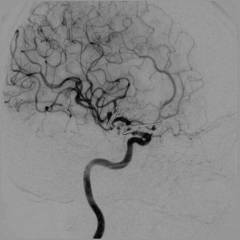

Ангиография головного мозга

Ангиография головного мозга, или церебральная ангиография – метод исследования сосудов головы для выявления патологий мозга.

Где вводят контрастное вещество? Процедура начинается с катетеризации плечевой, локтевой, подключичной или правой бедренной артерии. Катетер продвигается до места разветвления сосудов мозга, где вводится контрастное вещество.

Когда выполняется рентгенография? После первой порции контраста делают рентгеновскую съемку головы в нескольких проекциях (спереди и сбоку). Снимки анализируются сразу. Для исследования более удаленных участков вводится новая порция контраста, и съемка повторяется. Когда контраст проходит через ткани и попадает в вены, выполняется следующая серия снимков. На этом этапе катетер или пункционная игла удаляются, и процедура завершается.

Какие ощущения могут возникнуть во время процедуры? При катетеризации пациенту делают местную анестезию для обезболивания места введения. Боли при продвижении катетера не возникает, так как внутренние стенки сосудов не имеют болевых рецепторов. При введении контрастного вещества может появиться металлический привкус, ощущение тепла и покраснение лица. Эти симптомы обычно проходят через несколько минут.